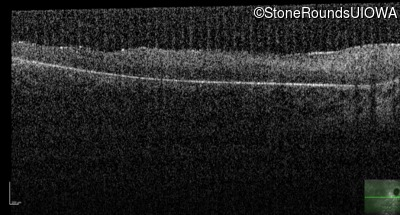

Age at visit: 7 years

OD OS

This 7 year old boy's mother first noticed that he was tripping over objects in dim light about one year ago.